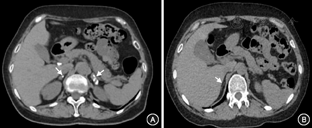

本组数据提示,艾迪生病病因中肾上腺结核感染42例,自身免疫性肾上腺炎27例,现将两组临床特点整理分析如下。肾上腺结核男性多见(男女比例1.5∶1),起病年龄(47.4±12.6)岁,最常见症状是乏力(71.4%),最常见体征为色素沉着(95.2%),血皮质醇149.6(87.5,233.5)nmol/L,ACTH>275 pmol/L有12例,占比为28.6%,ACTH<275 pmol/L者30例(71.4%),其ACTH为165.2(123.0,245.1)pmol/L,血钾、血钠、空腹血糖水平分别为(4.60±0.51)mmol/L、(134.3±6.8)mmol/L、(5.11±0.88)mmol/L;肾上腺CT阳性发现(增大、占位、钙化)率为95.2%,维持阶段氢化可的松用量为(30±7)mg/d。自身免疫性肾上腺炎方面,女性多见(男女比例为1∶2.4),起病年龄(37.0±10.6)岁,最常见症状是乏力(74.1%),最常见体征为色素沉着(100%),血皮质醇21.3(5.5,31.5)nmol/L,ACTH>275 pmol/L比例为44.4%,<275 pmol/L比例为55.6%,其ACTH为176.4(87.1,213.8)pmol/L,平均血钾、血钠、空腹血糖水平分别为(4.89±0.98)mmol/L、(131.7±8.1)mmol/L、(4.79±0.64)mmol/L;肾上腺CT阳性发现(增大、占位、钙化)率为11.1%(图1),维持阶段平均氢化可的松用量(32±9)mg/d。

进一步对肾上腺结核及自身免疫性肾上腺炎这两组人群临床特点进行比较,结果发现,结核好发于中年男性,自身免疫性肾上腺炎好发青年女性。与结核组患者相比,自身免疫组患者就诊时病情更重。此外,本组数据中自身免疫性艾迪生病患者TSH水平较结核组升高明显,一方面考虑与自身免疫组多合并自身免疫性甲状腺疾病,易引起TSH升高;另一方面也考虑与自身免疫组患者皮质醇缺乏更加明显,进一步促进了TSH的分泌有关。肾上腺CT检出率方面,结核感染多有肾上腺增大和钙化,故肾上腺结核感染CT多表现为肾上腺增粗、钙化(图1A),双侧多见,故阳性检出率较高(本组数据95.2%有阳性发现),需注意的是结核感染后期也有少数患者肾上腺缩小,故肾上腺CT无阳性发现不能除外结核感染,仍需结合病史并积极寻找其他结核感染证据。而自身免疫性肾上腺炎多表现为肾上腺纤细或无明显异常(图1B)。此外需注意的是肾上腺结核仅占双侧肾上腺病变的3.3%左右,发现肾上腺占位尚需考虑累及肾上腺的其他疾病[19]。部分CAH患者双侧肾上腺增生伴腺瘤变,部分也可伴钙化[20],这类患者多有性征发育异常,注意鉴别。